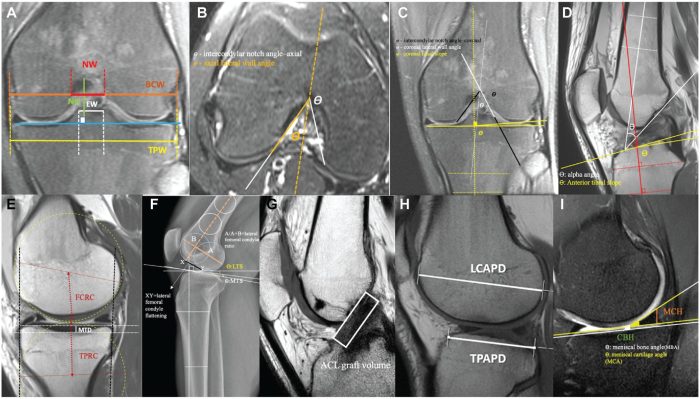

Measurement examples of main parameters. (A) Notch width (NW), eminence width (EW), notch height (NH), bicondylar width (BCW), and tibial plateau width (TPW). (B) Intercondylar notch angle–axial and lateral wall angle–axial. (C) Intercondylar notch angle–coronal, lateral wall angle–coronal, and coronal tibial slope. (D) Alpha angle and coronal tibial slope. (E) Medial tibial plateau depth (MTD), femoral condylar radius of curvature (FCRC), and tibial proximal radius of curvature (TPRC). (F) Lateral femoral condylar ratio, lateral femoral condyle flattening, lateral tibial slope (LTS), and medial tibial slope (MTS). (G) Anterior cruciate ligament (ACL) graft volume. (H) Lateral femoral condylar anteroposterior distance (LCAPD) and tibial proximal anteroposterior distance (TPAPD). (I) Meniscal cartilage angle, cartilage bone height (CBH), meniscal bone angle (MBA), meniscal cartilage angle (MCA), and meniscal cartilage height (MCH).